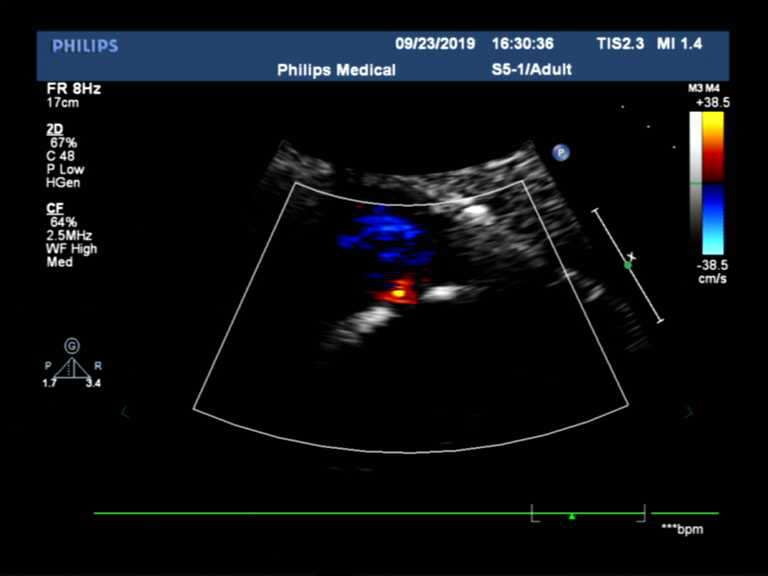

图片3.png

图三:右心声学造影见右向左大量微气泡

图一、图二高度怀疑卵圆孔未闭,结合临床表现(如不明原因头疼、青年人群的腔梗),建议经食管超声心动图和右心声学造影,下图为此患者诊断卵圆孔未闭提供了进一步的依据(右心声学造影见右向左大量微气泡)